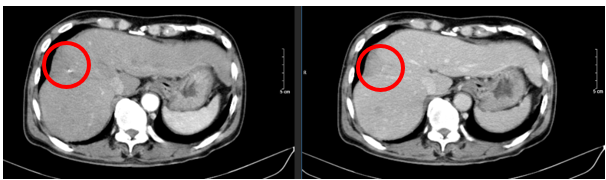

Ngày 19/06/2024: (sau 7 chu kì)

Hình 4: Hình ảnh chụp cắt lớp vi tính ổ bụng: Nhu mô vùng ngoại vi sát bao gan hạ phân thùy VII – VIII có đám (vòng tròn đỏ) giảm tỉ trọng kích thước ~ 28x36mm, trong có lắng đọng vật liệu nút mạch, không có huyết khối

Ngày 26/12/2024: (sau 17 chu kì)

Hình 5: Hình ảnh chụp cắt lớp vi tính ổ bụng: Nhu mô vùng ngoại vi sát bao gan hạ phân thùy VII – VIII có đám (vòng tròn đỏ) giảm tỉ trọng kích thước ~ 21x48mm, trong có lắng đọng vật liệu nút mạch, sau tiêm không ngấm thuốc, không có huyết khối.

Ngày 03/03/2025: (sau 20 chu kì)

Hình 6: Hình ảnh chụp cắt lớp vi tính ổ bụng: Nhu mô vùng ngoại vi sát bao gan hạ phân thùy VII – VIII có đám (vòng tròn đỏ) giảm tỉ trọng kích thước ~ 22x45mm, trong có lắng đọng vật liệu nút mạch, sau tiêm không ngấm thuốc, không có huyết khối.

Nhận xét: Bệnh nhân đạt đáp ứng tốt với điều trị: khối u thu nhỏ kích thước đáng kể sau 20 chu kì (từ 81x51mm xuống 22×45 mm). Đánh giá theo tiêu chuẩn RECIST 1.1, bệnh đáp ứng một phần (PR – Partial Responce).